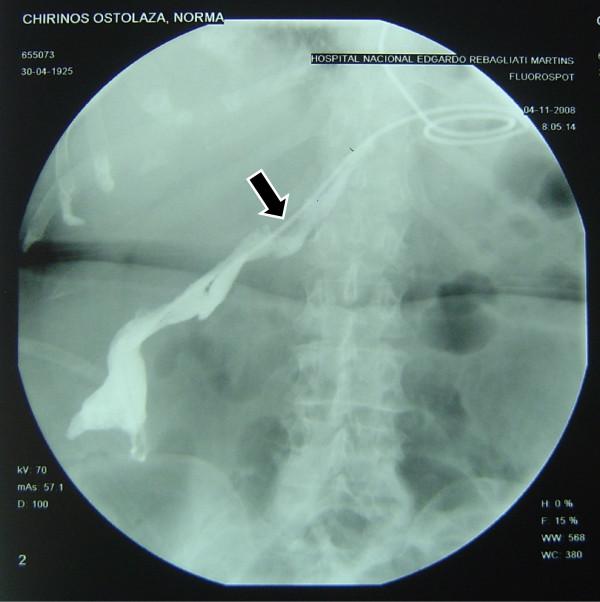

Between January 2004 to December 2008, 588 consecutive patients with a proven diagnosis of gastric cancer were taken to the operation room to try a curative treatment. Of these, 173 underwent total gastrectomy, 9 of them had esophagojejunal fistula (5.2%). In three selected patients a trans-anastomotic naso-enteral feeding tube was placed under fluoroscopic vision when the fistula was clinically detected and a complete polymeric enteral formula was used.

The complete closing of the esophagojejunal fistula was obtained in day 8, 14 and 25 respectively.

In some selected cases it is possible to make a successful enteral nutrition using a feeding tube distal to the leak area inserted with the help of fluoroscopic vision. The specialized management of a gastric surgery unit and nutritional therapy unit are highlighted.